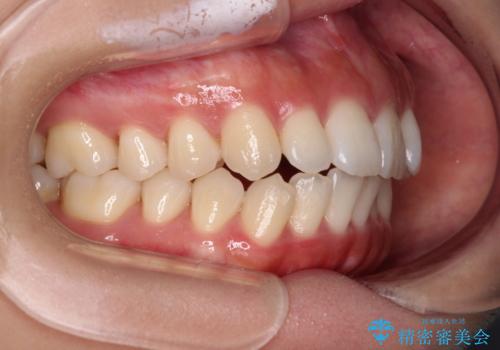

- 上下前歯の隙間と口元の出っ張った感じを気にして来院された患者様です。

上下の隙間は舌突出癖によるもので、またその癖により前歯が前方に出ている状態でした。

口元の出っ張りを改善するため、上下左右第一小臼歯4本を抜去し、ワイヤー装置にて矯正治療を行うこととしました。